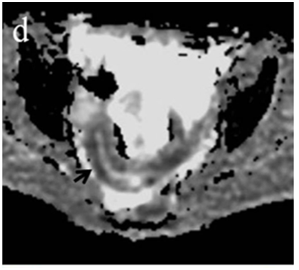

Figure 4 (a) Coronal SSFSE (singleshot fast spin echo) T2-weighted image with fat suppression (b) axial FIESTA (fast imaging employing steady-state acquisition) image show wall thickening (white arrow) and stenosis of the lumen in the terminal ileum. Note the prestenotic dilatation in b (white arrowhead). (c) Neoterminal ileum wall is thickened and has high signal on diffusion-weighted (DW) image (b= 800 s/mm2) (white arrow) and dark signal (black arrow) on the apparent diffusion coefficient (ADC) map in (d) indicating restricted diffusion. (e,f) ADC value measurement from the wall of the terminal ileum on magnified DW image. (e) and corresponding ADC map (f): ADC value = 1.20 × 10-3 mm2/s